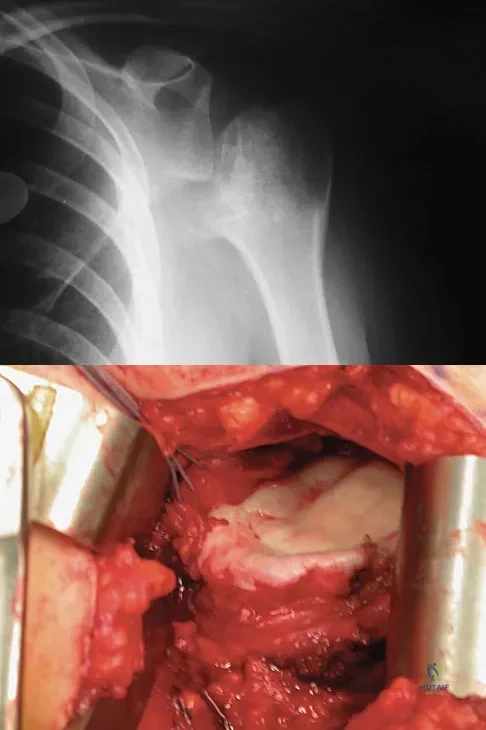

Question 70

A 28-year-old man sustained a shoulder dislocation 2 years ago. It remained dislocated for 3 weeks and required an open reduction. He now reports constant pain and has only 60 degrees of forward elevation and 10 degrees of external rotation. He desires to return to some sporting activities. An AP radiograph and intraoperative photograph (a view of the humeral head through a deltopectoral approach) are shown in Figures 31a and 31b. What is the best treatment option to decrease pain and improve function?